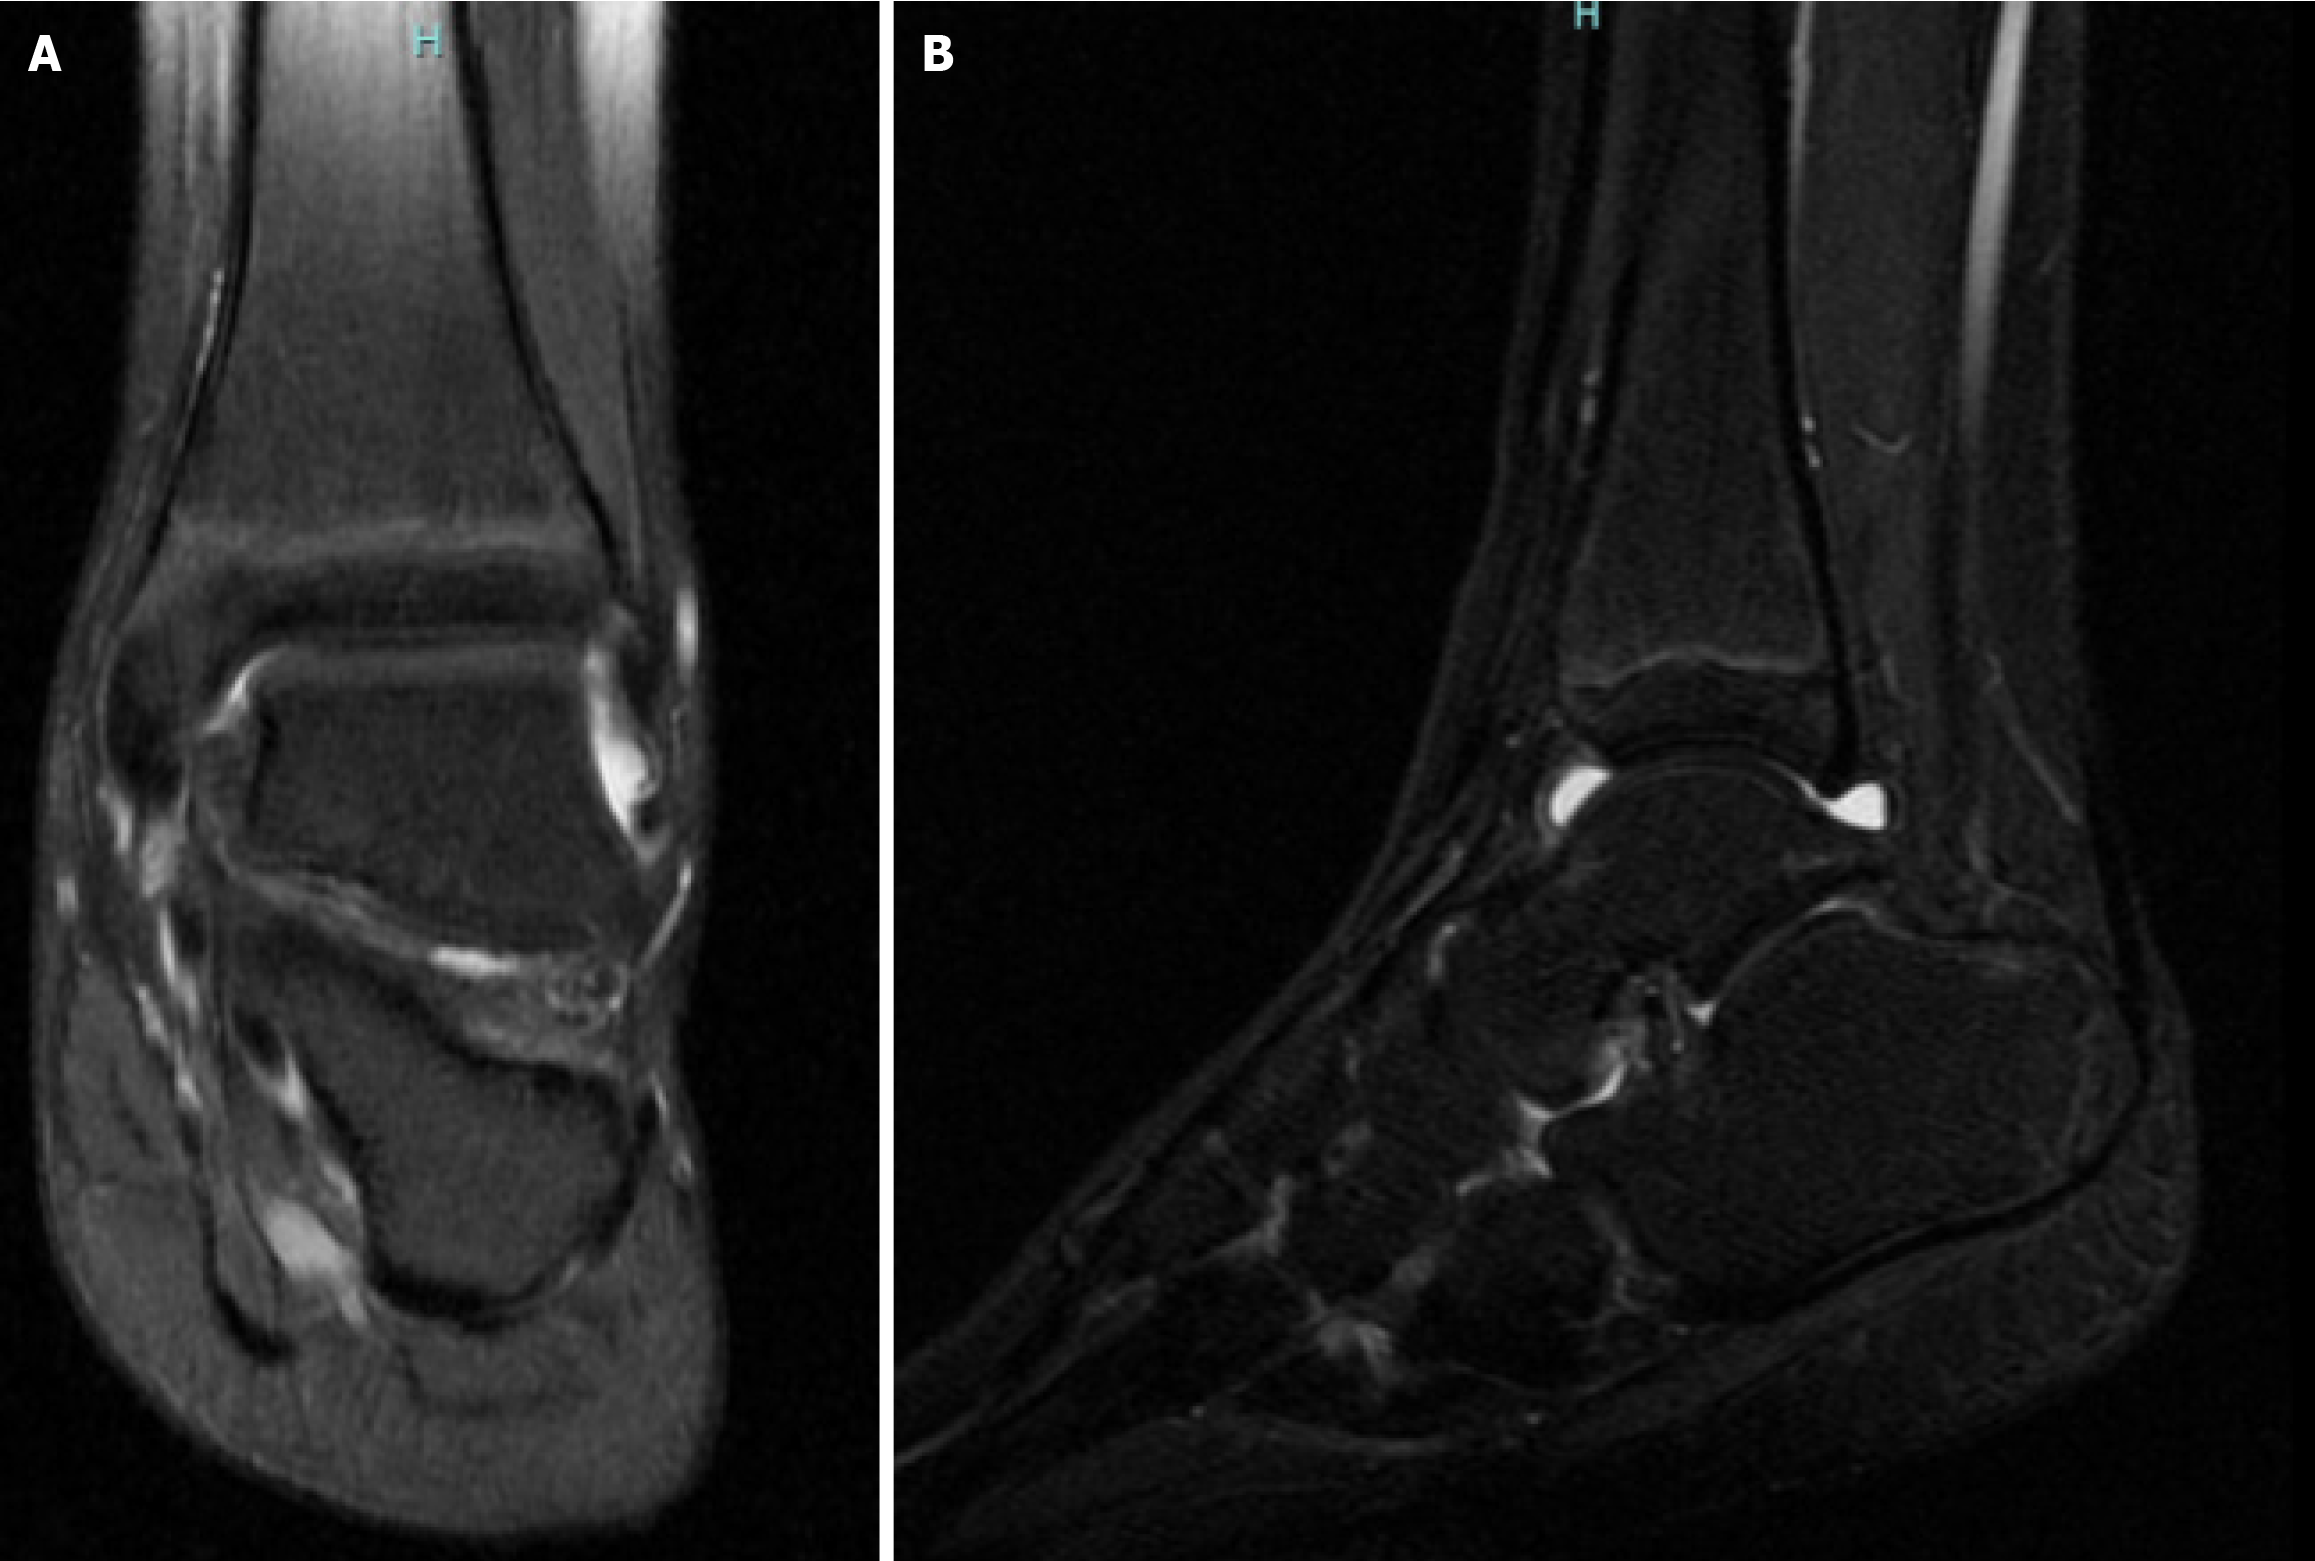

Figure 1 Magnetic resonance imaging of the left foot and ankle joint.

A: Posterior view; B: Lateral view.